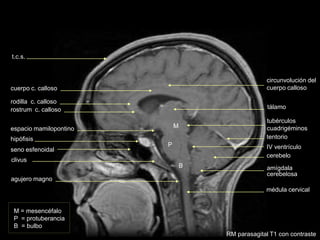

rostrum c. calloso

rodilla c. calloso

cuerpo c. calloso

clivus

seno esfenoidal

hipófisis

tallo pituitario

tentorio

seno sagital

superior

diploe

t.c.s.

acueducto de Silvio

RM sagital T1 con contraste

cuerpo mamilar

cavum

M = mesencéfalo

P = protuberancia

B = bulbo

M

P

B

médula cervical

amígdala

cerebelosa

IV ventrículo

tálamo

cerebelo

tubérculos

cuadrigéminos

espacio mamilopontino

circunvolución del

cuerpo calloso

agujero magno

RM parasagital T1 con contraste